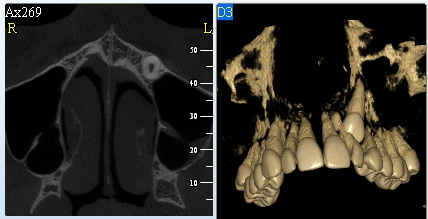

Pomocí tohoto přístroje je možné zjisti skutečnou situaci v čelistních kostech pacienta tedy množství kosti - můžeme změřit skutečnou šířku i výšku kosti, i kvalitu kosti (hustotu) v místě uvažované implantace. 3D (tříprostorové) zobrazení umožňuje

zvýšit prostorovou představu operatéra ještě před vlastní operací a zároveň pacientovi lépe objasnit a ukázat oblast plánovaného zavedení implantátu.

Pacient „neumí číst“ RTG snímky, ale díky 3D zobrazení vidí „svoji skutečnou čelist“ – např. jak je nízká či úzká, vidí průběh nervu nebo velikost čelistní dutiny, což mu umožní i pochopení nutnosti v některých případech provést pomocné zákroky

ještě před vlastním zavedením implantátu (více - Augmentace - kostní štěp, sinus lift, kostní granulát...).

Jedná se o plánovací program, který využívá dat získaných při vyšetření pomocí přístroje New Tom. Tento program umožňuje tříprostorovou počítačovou simulaci při plánování pozic implantátů.

Součástí programu je i databáze, ve které mohou být uloženy všechny typy implantátů od všech výrobců, včetně jejich délek, průměrů i tvarů.

Lékař si vytvoří všechny typy zobrazení potřebných pro naplánování – tedy 2D snímky (panoramatický), příčné řezy i 3D model.

Vidí zde i důležité anatomické útvary – čelistní dutinu, průběh nervu atd. Po proměření množství kosti – šířky i výšky vybere z databáze vhodný typ implantátu a umístí ho do požadované lokality.

Ihned vidí jeho pozici ve všech 3 rovinách a na všech snímcích i 3D modelu. Může upravovat podle potřeby jeho pozici, sklon atd.